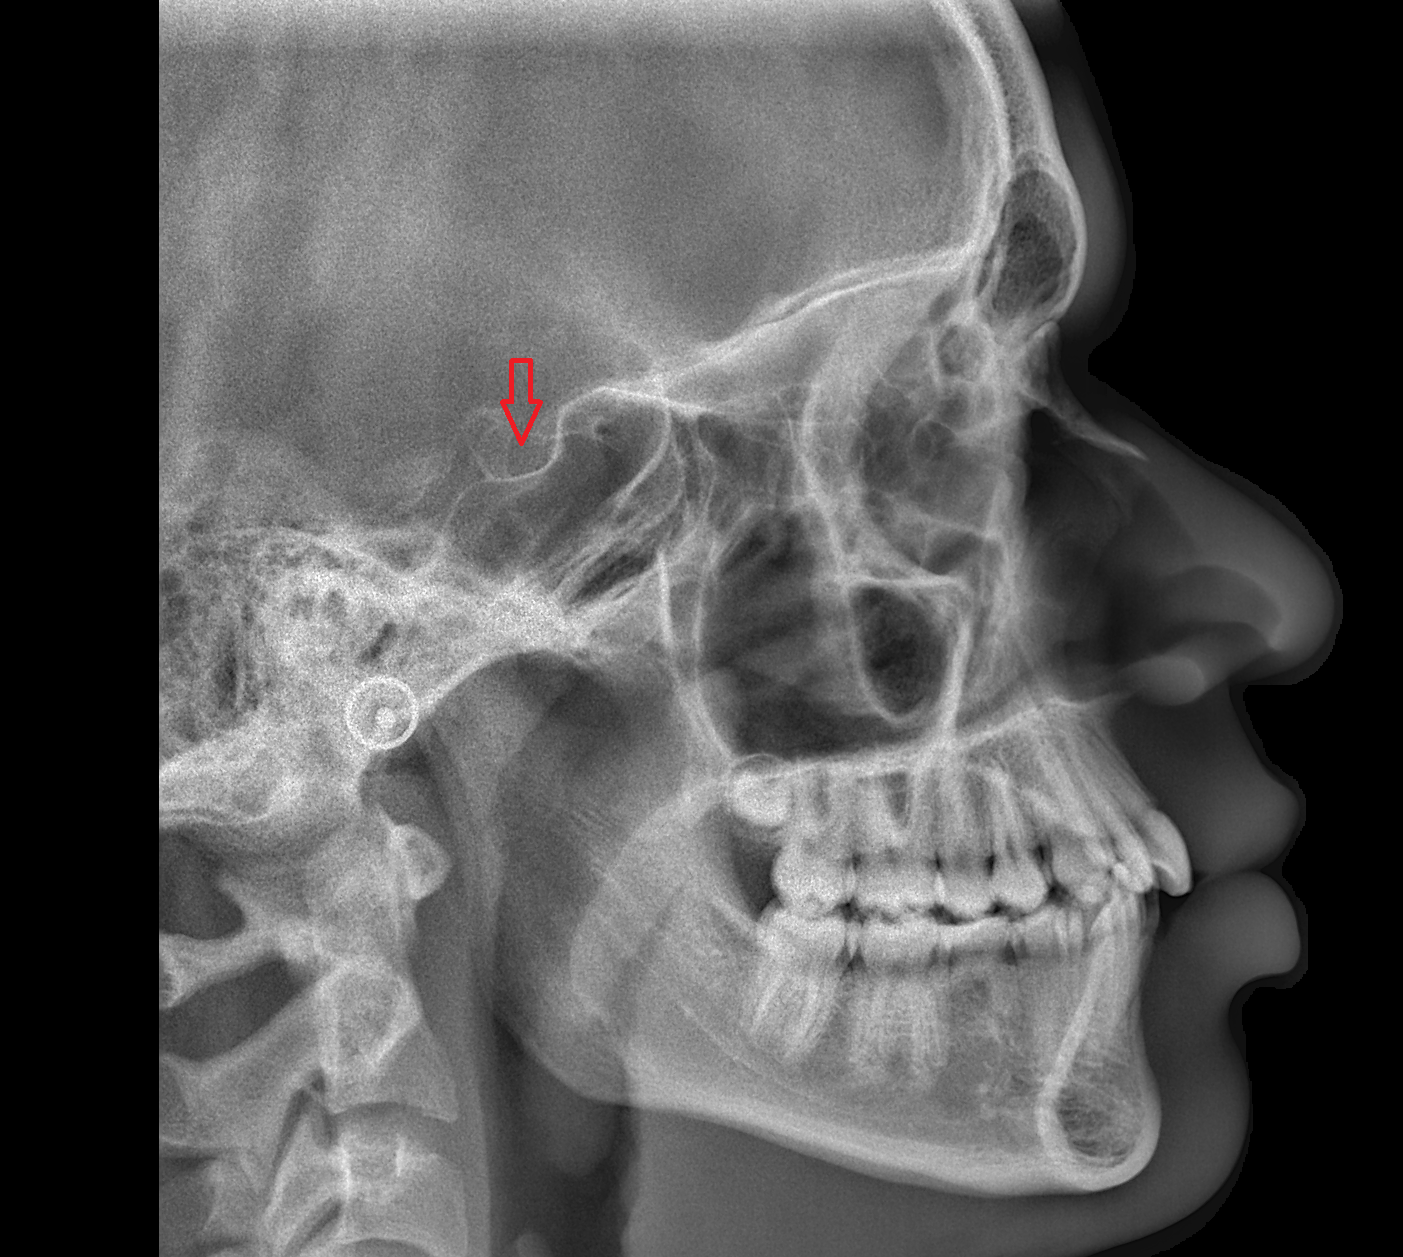

- Temporomandibular joint

- Mandibular condyle

- Mandibular fossa

- Articular eminence

- Articular tubercle

- Mastoid process

- Squamous part of temporal bone

- Zygomatic process of temporal bone